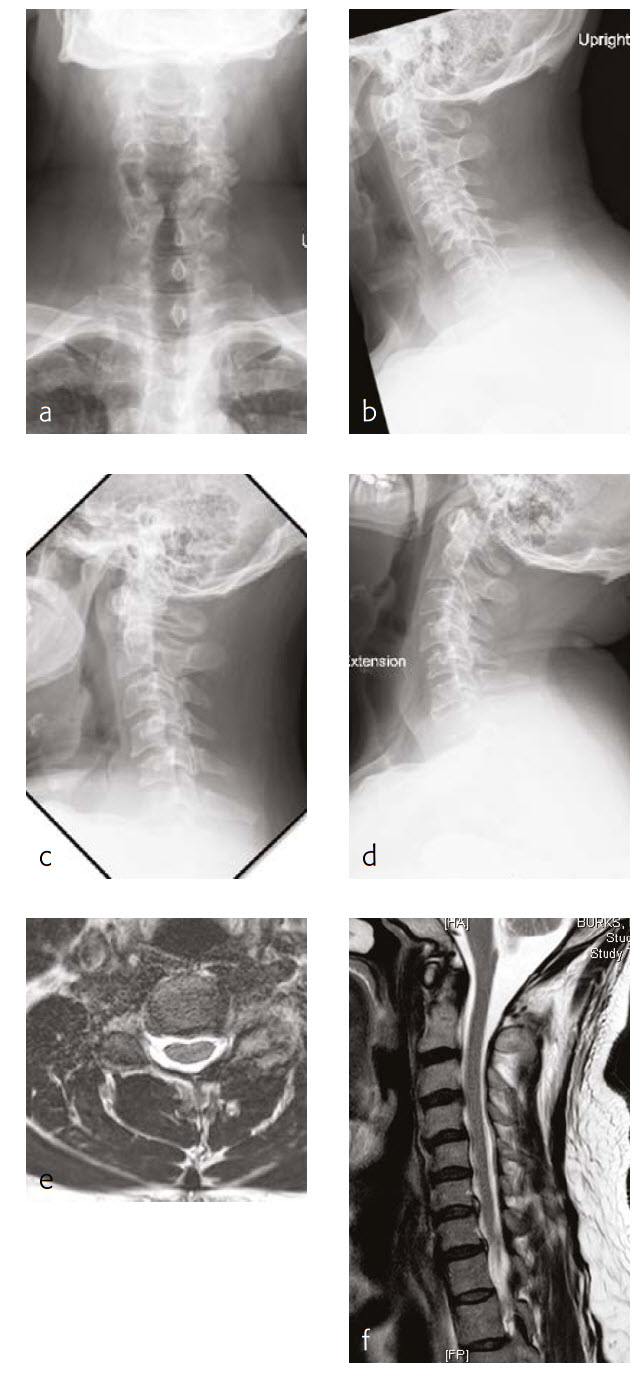

A 56-year-old man, partly left-hand dominant partly right-hand dominant depending on the activity, presented with progressive left shoulder and arm weakness with pain radiating from his neck down to his left shoulder and an EMG documenting a left C5 radiculopathy (Fig 1).

The patient claimed a normal state of health until 5 weeks previous. This then began to backtrack to the neck and to develop weakness in his left arm to the biceps and deltoid. On examination, the patient had 4/5 deltoid and biceps strength on the left and decreased sensation along his lateral shoulder.

The patient showed normal lordosis in his extension x-rays. He has approximately 2 mm of anterolisthesis of C4 on C5 in his extension on his flexion x-ray. This increases to approximately 56 mm and persists in his normal upright film with again some component of spondylolisthesis at that level.

The patient's earlier MRI shows severe left-sided C4-C5 foraminal stenosis and multilevel disc degeneration with very mild central narrowing at C3-C4, C6- C7, and C7-T1. He also has a small right paracentral disc herniation at C6-C7.

The new MRI of the C4-C5 showed mild uncovering of the disc posteriorly due to grade 1 anterolisthesis. There is also mild left facet arthropathy with left uncovertebral joint osteophytes resulting in moderate left neural foraminal narrowing. The right neural foramen is adequately patent.